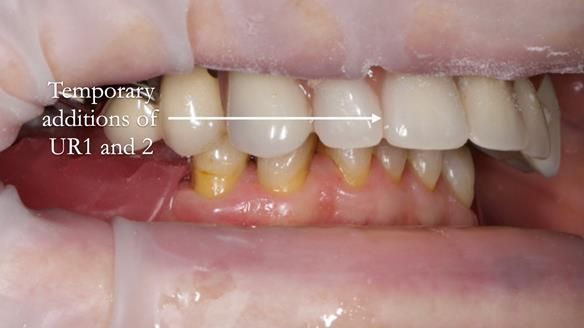

- Add upper right lateral and central incisor denture teeth to existing upper RPD as temporary measure during making of new RPDs

- The upper right central and lateral incisors with post crowns. Healthy and functionally secure but with poor appearance, contributing to the reverse curve.

- Upper and lower metal based RPDs, poorly fitting, worn occlusal surface, reverse curve aesthetics, lacking support